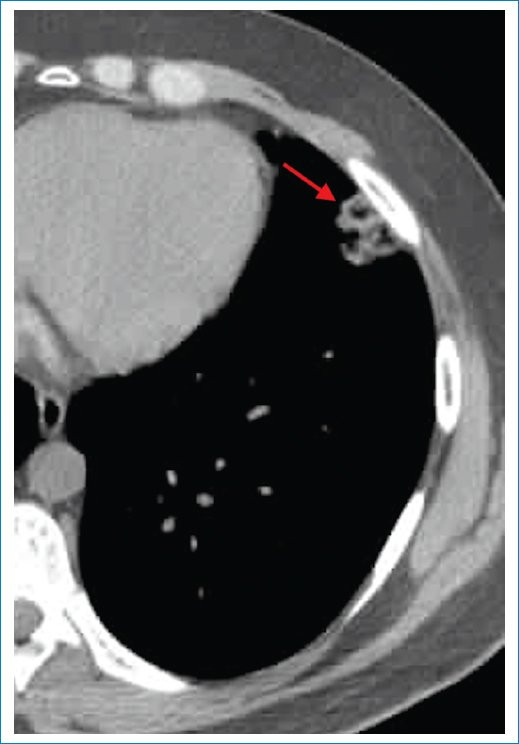

- Signo del vaso nutricio: muestra una especificidad del 89% y una sensibilidad del 32%7. Consiste en la presencia de un vaso pulmonar engrosado y bien diferenciado que se dirige directamente a un nódulo u opacidad pulmonar. Se observa también en casos de metástasis hematógenas y embolias sépticas, por lo que no es un signo exclusivo de IP; sin embargo, en el contexto clínico adecuado incrementa su sensibilidad (Fig. 4)8.